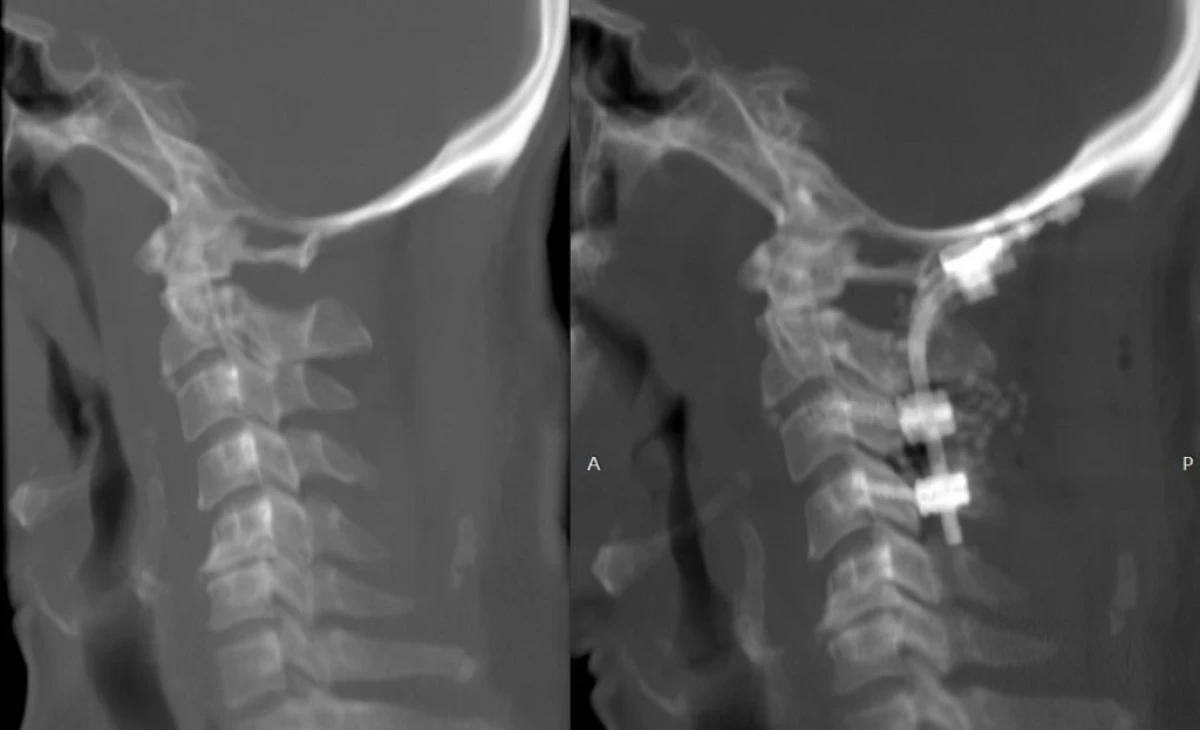

Occipito-cervical fusion surgery Xray --- Photo: IGMH

The department successfully carried out its first occipito-cervical fusion surgery, a highly complex operation performed to stabilise the junction between the skull and cervical spine. This procedure is often necessary in cases of severe instability caused by trauma, congenital anomalies, or degenerative disease.